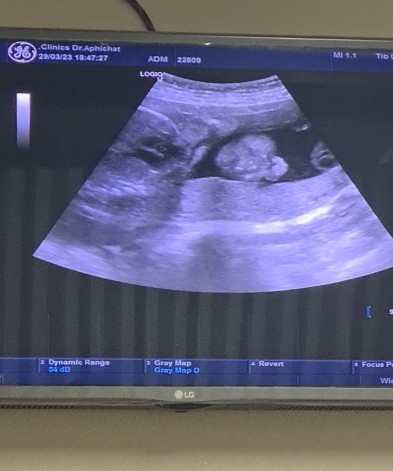

ตอนนี้ ท้อง 25W น้ำหนักน้อง 950g ถือว่าอยู่ในเกณฑ์มั้ยคะ หรืออ้วนไปมั้ย 😍

ไปหาลุงหมอเมื่อวาน เมื่อ 27 วันก่อนลุงหมอนัด น้องยังมีน้ำหนัก 540g อยู่เหลย เมื่อวานไปหาลุงหมอ คือ 😍 ตรงกับ 25w 5 วัน น้องน้ำหนักพุ่งไป 950g ถือว่า ปกติใช่มั้ยคะ 😁 เทียบน้ำหนัก 27 วันที่ผ่านมา - 29/3 แม่ 49.8 / 50.6 ลูก 540g / 950g คะ